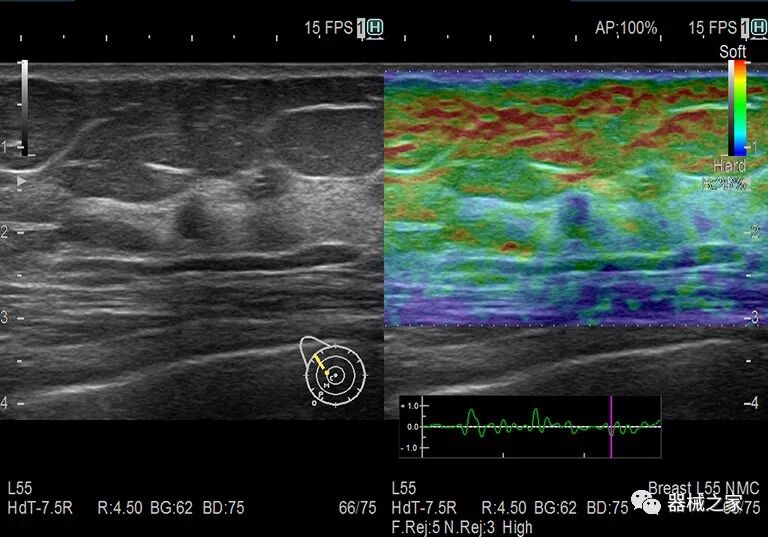

在几年前,超声波无法对小型慢流血管中的血流进行成像,但现在有少数供应商提供具有此功能的系统。该特征提供了另外一种检查病变以指示癌症或炎症的方法。其中一个是佳能Aplio 900 CV系统,它可以显示毛细血管中的血流量。日立的Arietta 65中程系统提供了一种可视化小血管的功能,可以更好地观察肾脏等器官的灌注情况。三星RS85还提供MV-Flow可视化慢流微血管结构。